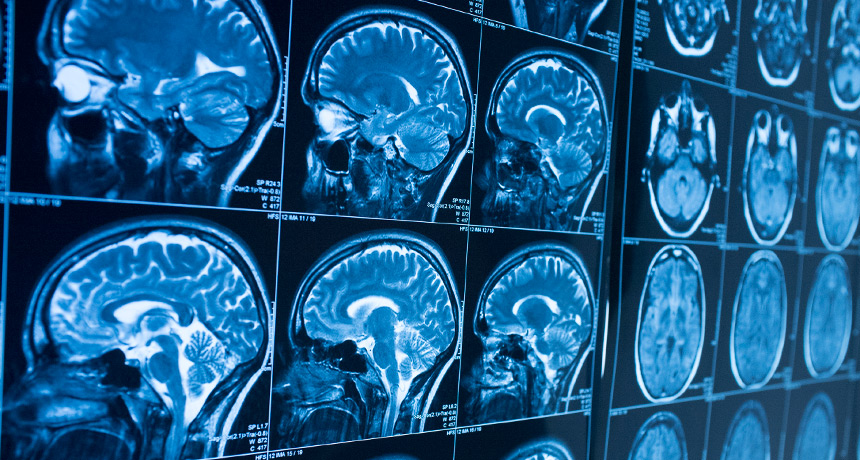

Using scans of brain activity, scientists were able to show that how teens’ brains process emotions changes as they mature.

All her team’s recruits were 14 years old. During tests, each lay very still inside an fMRI scanner. (That acronym stands for functional magnetic resonance imaging.) This machine uses powerful magnets to measure blood flows throughout the brain. As the brain takes on tasks, such as reading or managing emotions, blood flow can increase or decrease in different areas. This points to which parts of the brain are most active.